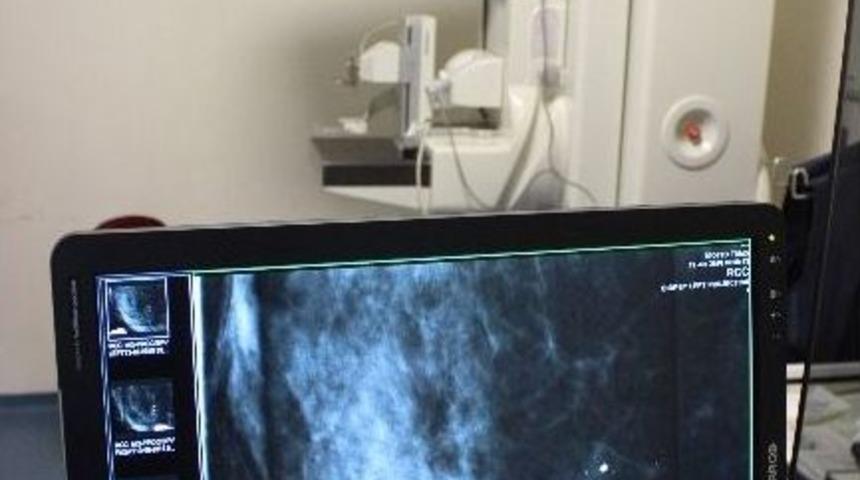

Bursa’ya italya’dan getirtilen stereotaktik cihazı sayesinde meme kanseri ilerlemeden erken teşhis edilecek.Ali Osman Sönmez Onkoloji Hastanesi İtalya’dan getirdiği meme kanseri tarama cihazıyla hastalara erken teşhis yaparak meme kanserinden ölümleri en aza indirecek. Cihazla ilgili bilgi veren Bursa Ali Osman Sönmez Onkoloji Hastanesi Başhekimi Dr. Oktay Çelik, “Geçen yıl Sağlık Bakanlığı tarafından Bursa Ali Osman Sönmez Onkoloji Hastanesi’ne kurulan Dijital Mamografi (DMG) cihazına biz de hastanemizin imkanlarıyla Stereotaktik Biyopsi Ünitesini kazandırdık. Bu, Bursa’da bir ilktir. Aktif olarak bu işlemleri yapabilen Bursa’da ve çevre illerde de tek merkez konumuna gelmiş bulunmaktayız. Bursa’da kamu hastanelerindeki tek olan bu cihaz sayesinde meme kanseri teşhis ve tedavisinde daha güzel hizmet vereceğiz. Hasta adaylarına erken teşhisle erken müdahale edip meme kanserinden koruyacağız. Ben 40 yaşın üzerindeki tüm hastalara meme kanseri taraması yapmalarını öneriyorum. Özellikle ailesinde meme kanseri hastalığına yakalananların mutlaka tarama yaptırmaları gerekir” dedi.